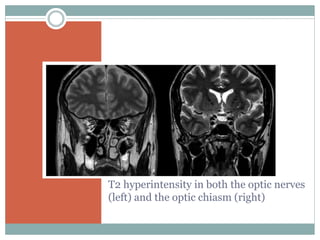

 MRI

T2 hyperintensity in both the optic nerves

(left) and the optic chiasm (right)